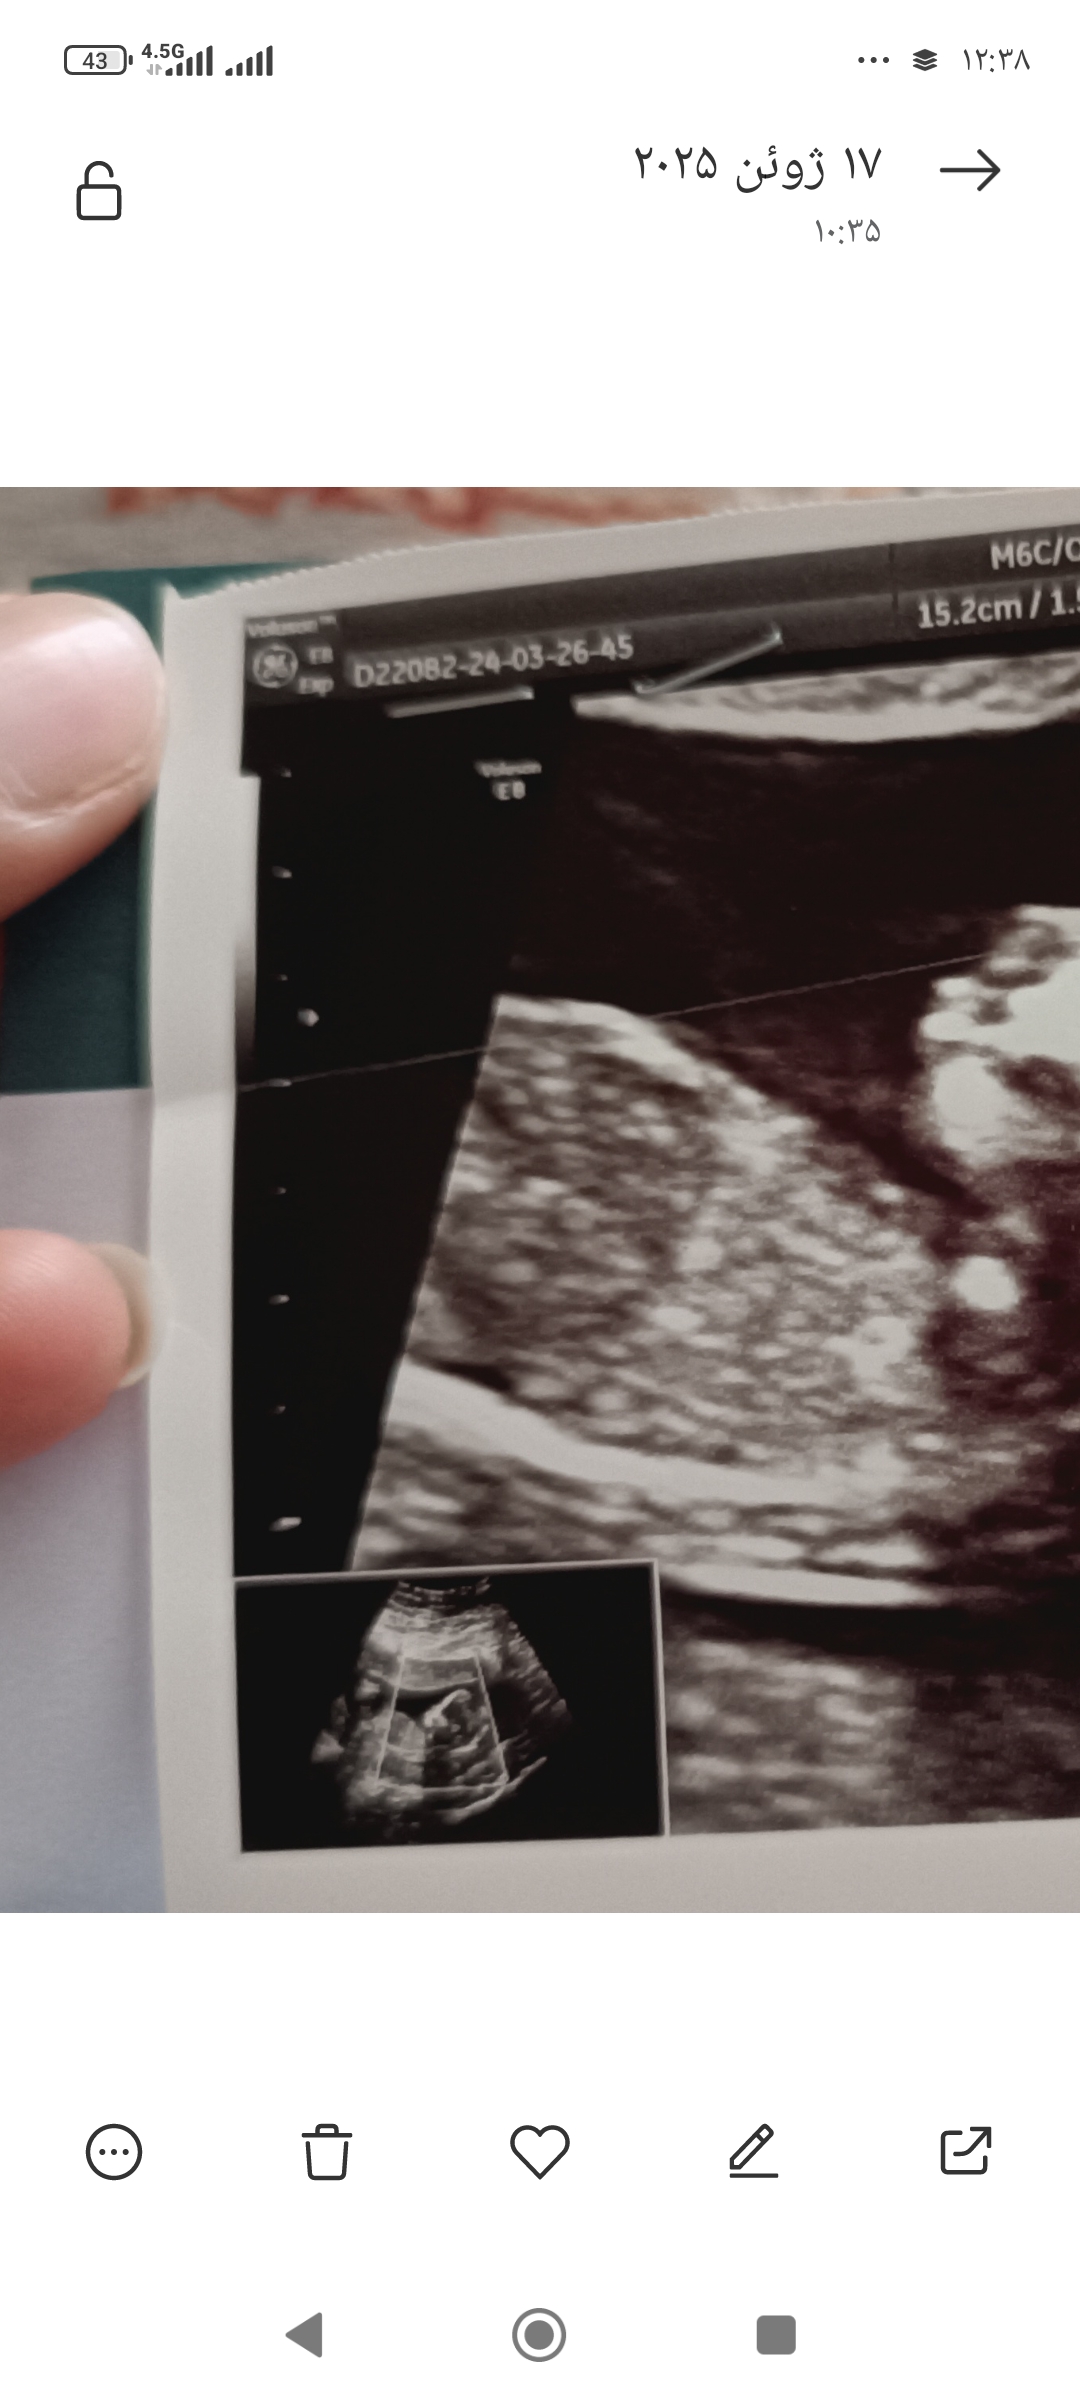

arsin02 مدیر استارتر عضویت: 1404/03/27 تعداد پست: 16 عنوان تو دلیم چیه 🥲🥲 52 بازدید | 2 پست سلام از بس بهش فک کردم داغون شدم کسی میتونه از روی عکس nt تشخیص جنسیت بده 1404/04/04 | 12:30 0 نفر لایک کرده اند ... گزارش تاپیک نامناسب

دلبر_گلگلی عضویت: 1404/03/12 تعداد پست: 5287 بفرس فقط 27 هفته به تولد باقی مونده ! 1 5 10 15 20 25 30 35 40 🌷تیکر کنکورمه🌷